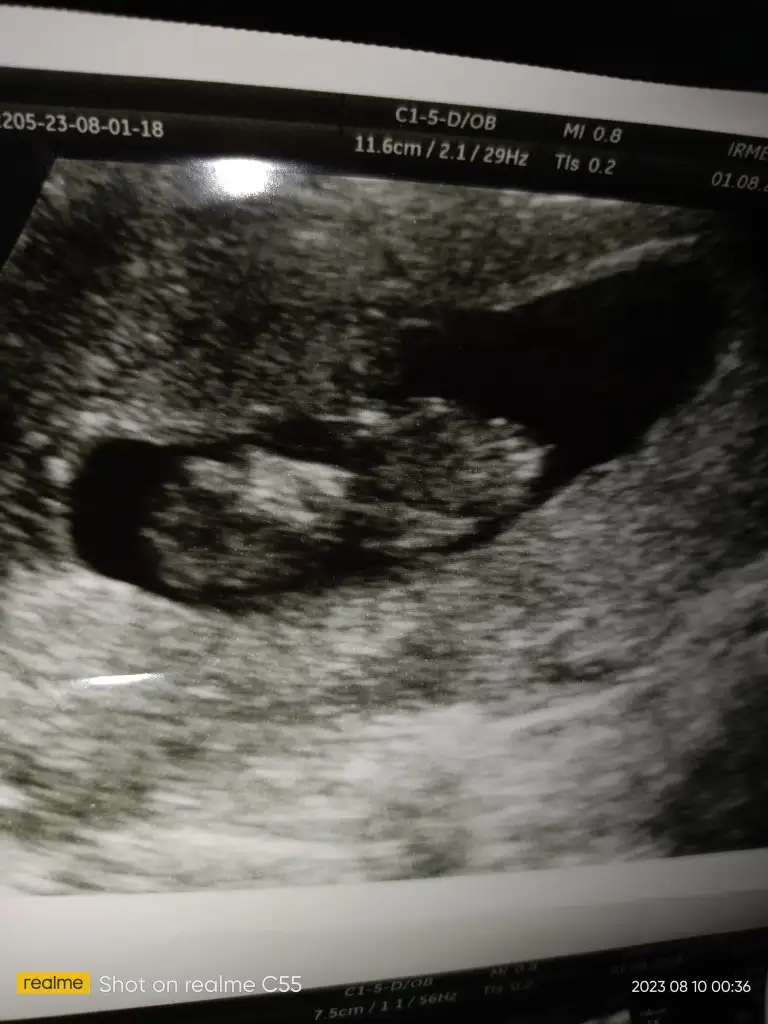

12+4 doktor pipiye benziyor ama kıza da benziyor duruşu dedi tam belli değil yani dedi sizinde tahmininiz alıyımSağlıkla gelsin inşallah bebecik.

Gerçekten de ikisini de andırıyor ama ben nedense hala kızda yoğunlaşıyorum. Rabbim hayırlı olanı nasip etsin inşallah canım, sağlıklı güzel ahlaklı bir evladın olsun.12+4 doktor pipiye benziyor ama kıza da benziyor duruşu dedi tam belli değil yani dedi sizinde tahmininiz alıyım